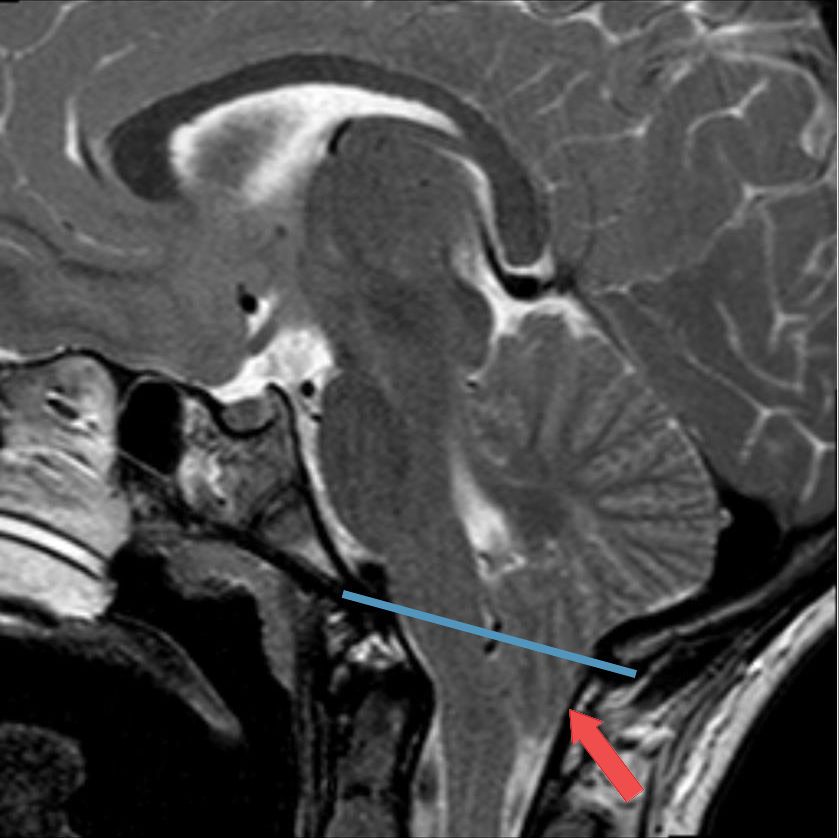

MALFORMACIÓN (CHIARI)

La malformación de Chiari es una condición poco común en la que el tejido cerebral se extiende hacia el canal espinal.

Esta condición puede causar una variedad de síntomas y requiere una evaluación y tratamiento especializados.